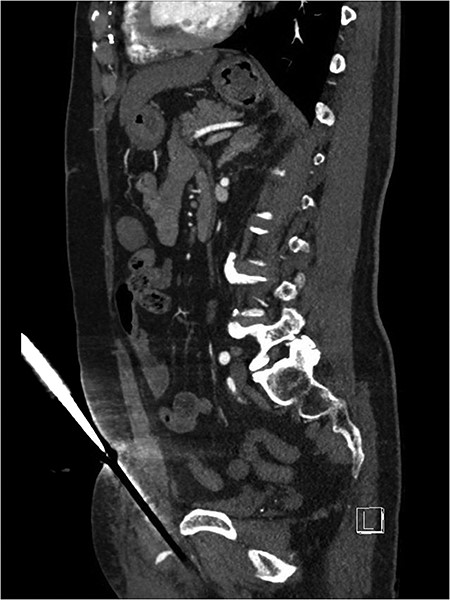

After discussion with urology, a 14Fr indwelling catheter was inserted, which drained yellow urine. A computed tomography (CT) mesenteric angiogram demonstrated penetrating injury to the suprapubic region with haematoma and two foci of arterial extravasation with radiological evidence of peritoneal breach, and the metallic foreign body in situ (Figs 2 and 3). Importantly, the tip of the knife appeared to end at the base of the penis at the expected confluence of the dorsal vein.

Suprapubic stab wound: sagittal section: CT mesenteric angiogram showing knife directed in infero-posterior direction abutting but not traversing the peritoneum. Active arterial contrast extravasation can be seen. The tip of the knife abuts the root of the penis.